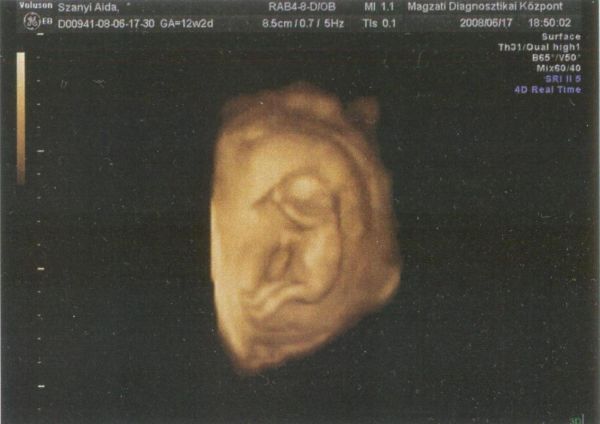

zümis: Jól telnek a napok, az első trimesztert megúsztam kb. 2-3 kicsit émelygős nappal meg pár gyomorsavas estével, de egyébként semmi egyéb. Ti hogy vagytok így az első trimeszter közepe táján? Most a 14. hétbe lépve nálam kezd előjönni a "barnamaci nem jön rendszeresen probléma" amire mondta az orvos, hogy azért van mert a méh már kilépett az üregéből és nyomja a beleket. No ez nem hiányzik, de egyébként tök jó minden. Amúgy kismanó növöget, megmutatom Nektek is, 13+2 (orvosi vizsgálat szerint 13+5) naposan a picurkánk:

Kép Kismanó